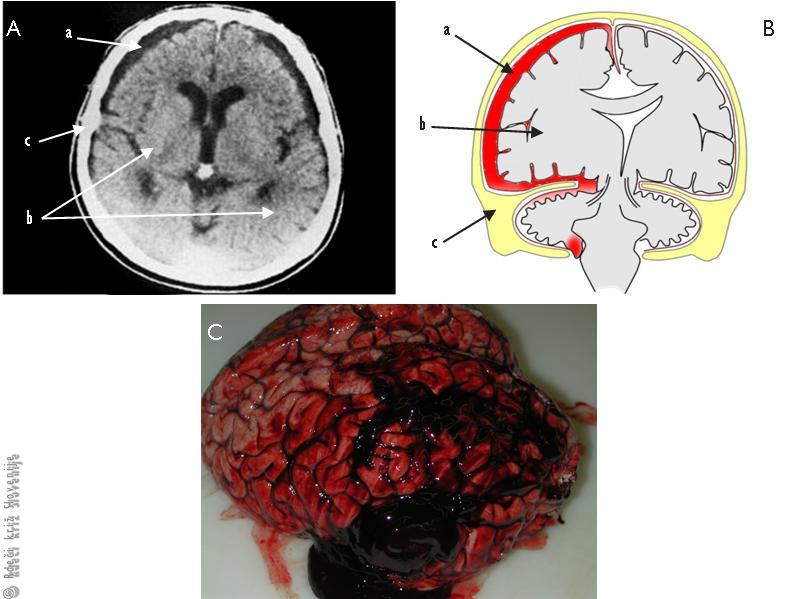

Slika 1

Subduralna krvavitev.

A – Globinsko slikanje.

B – Shematični prikaz stanja – vzdolžni prerez, ki lahko takoj ali čez čas povzroči zoženje zavesti (a – krvavitev, b – možgani, c – kost).

C – Slika subduralnega hematoma pri obdukciji.